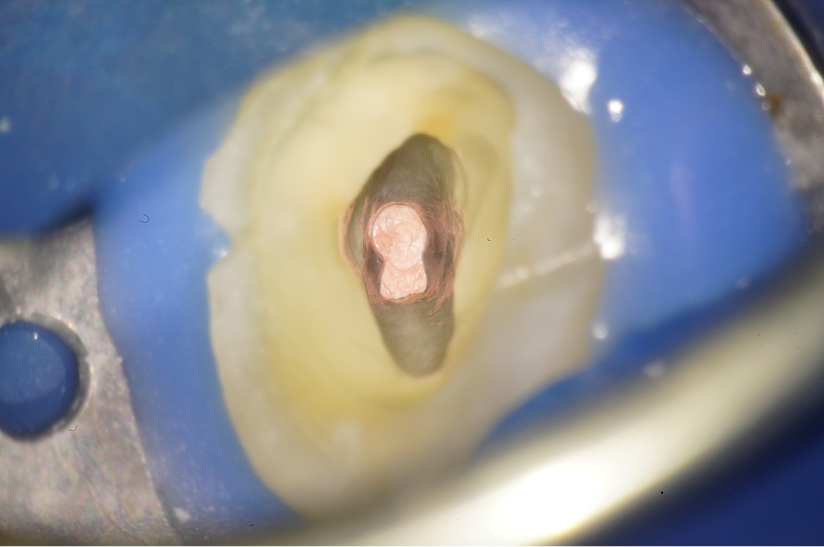

親知らずを活用し天然歯を保存した症例

タップで写真の拡大ができます。

Before

Under Treatment

After

主訴

インプラントはできないが、入れ歯もしたくない

治療内容

自家歯牙移植 / イニシャルトリートメント(大臼歯)レジンコア

治療期間

3ヶ月

治療費用

550,000

治療の

リスク

術後しばらくしてから骨性癒着、外部吸収を起こす可能性があります。